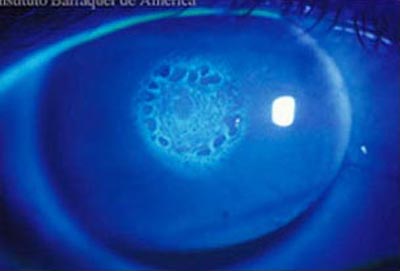

Endoteliografía

Endoteliografía

Siendo la capa más interna de la córnea, está en contacto con el humor acuoso y forma la pared de la cámara anterior; Está compuesta por células hexagonales distribuídas en una sola capa con una cantidad promedio de 2.500-3.000 células por mm2. Van disminuyendo con la edad. Permite el paso de nutrientes al interior de la córnea y controla su estado de deshidratación, siendo por lo tanto la capa responsable de mantener la transparencia corneal. El endotelio tiene muy escasa capacidad de regenerarse por lo que no es capaz de reparar por división un defecto en su extensión, lo cual hace agrandando y extendiendo sus celulas.